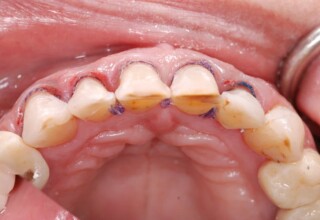

Porcelain Veneers

The best way to solve esthetic problems of the anterior teeth. They combine very little tooth grinding with very high esthetic performance. In the following extensive case anterior teeth presented with: old restorations, staining, poor shape, length and tooth –gingiva ratio. Meticulous diagnostic waxing was performed on study casts and temporary veneers were manufactured. Temporary veneers were used intraorally to evaluate the incorporated changes and to further modify and adjust were needed. When esthetics and function were approved by the patient and were satisfying for the operator the temporaries were used as a guide for the final porcelain veneers. The five final veneers on the upper anterior teeth restored the smile of the patient to almost perfection.

Initial appearance

Final appearance